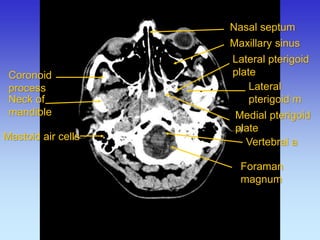

Coronoid process

Neck of mandible

Lateral pterigoid m

Lateral pterigoid plate

Medial pterigoid plate

Maxillary sinus

Nasal septum

Mastoid air cells

Styloid process

Spinal card

Foraman magnum

Vertebral a